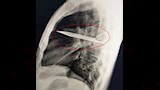

في واقعة طبية نادرة، اكتشف أطباء في تنزانيا شفرة سكين معدنية كبيرة مستقرة داخل تجويف صدر رجل يبلغ من العمر 44 عاما، بعد مرور ثماني سنوات على تعرضه لطعنات متكررة دون أن يعلم ببقاء الشفرة في جسده.

وأظهرت الفحوص السريرية أن الجزء الأيمن من صدره لا يتمدد بالكامل أثناء التنفس، فيما كشفت الأشعة السينية وجود شفرة سكين كبيرة عالقة في تجويف الصدر، ممتدة من الظهر إلى مقدمة القفص الصدري، ومحاطة بطبقات من القيح والأنسجة الميتة.